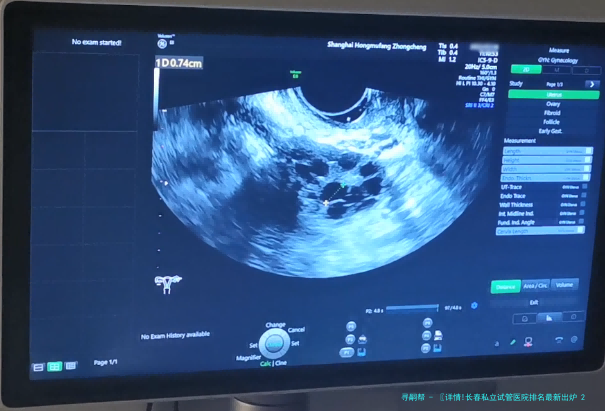

试管婴儿过程中,胚胎是在实践室里培养的,因此实践室的水平从某种程度决定了胚胎的潜力。您可以尝试了解试验室的配置,例如胚胎培养箱的品牌和数量、是否备有胚胎冷冻保存和复苏本事等。一个设备精良、由经验丰富的胚胎研究者管理的试验室,是成功的首要保障。